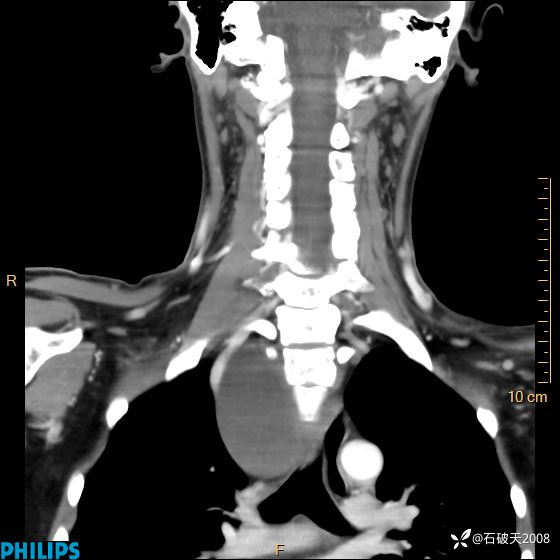

动脉期

冠状位